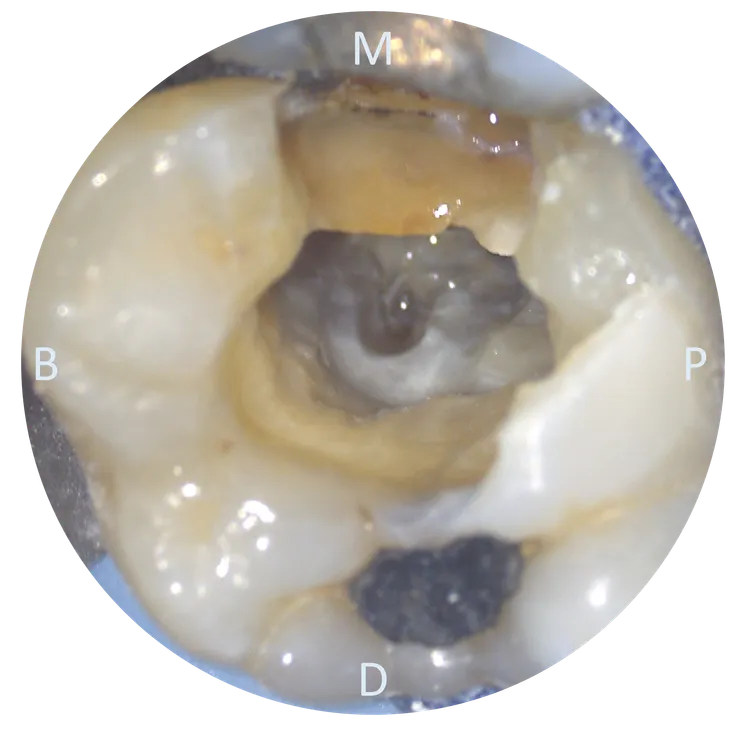

把 CBCT 的資訊記在腦中後,我們轉移到顯微鏡下來看看實際的情況:

可以看到用了五年的 temporary crown 下已經養出了一推 caries......

先把 caries 挖乾淨後再開始 retreat.

這次主要 focus 在箭頭所指的 ML canal.

把舊 GP 大致移除後,幸運地在根管壁上看到一個突兀的洞 (紅色箭頭所指),剛好就位於原本路徑 (粉紅色箭頭) 的 DB side !

顯微鏡下看起來是什麼樣子呢?

垂直咬合面看進去,可以在 floor DB corner 看到一個疑似 DB orifice 的白點,但 file 在很淺的地方就卡住戳不進去了,似乎跟上頁圖中 file 進去的深度不符合?

偏個角度由 MP 往 DB 看,發現那個白點的 DB side 還有個凹陷處!這裡才是真正的 orifice !